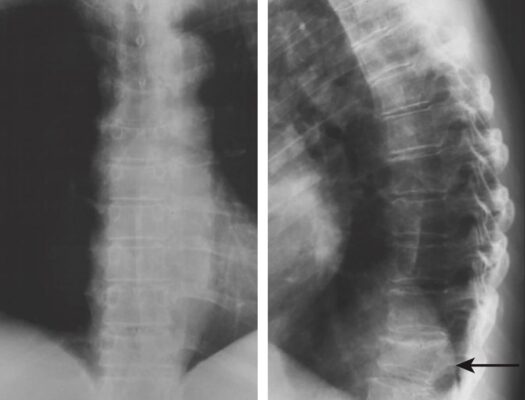

- X quang ngực thẳng và nghiêng là xét nghiệm có giá trị chẩn đoán, phát hiện đốt sống bị giảm chiều cao, thường có dạng hình nêm, với chiều cao phía trước nhỏ hơn chiều cao đốt sống sau. Trong bệnh loãng xương, X quang cũng có thể phát hiện đốt sống bị biến dạng lõm hai mặt.

- Chụp CT scan hoặc cộng hưởng từ (MRI) được chỉ định khi cần làm rõ thêm chi tiết, nhất là khi nguyên nhân do chấn thương nặng, đau ở vị trí bất thường (ví dụ ở đốt sống ngực cao), có dấu hiệu tổn thương thần kinh hoặc nghi ngờ bệnh lý khác.